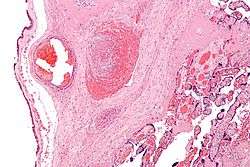

Once a person is diagnosed with cerebral palsy, further diagnostic tests are optional. Neuroimaging with CT or MRI is warranted when the cause of a person's cerebral palsy has not been established. An MRI is preferred over CT due to diagnostic yield and safety. When abnormal, the neuroimaging study can suggest the timing of the initial damage. The CT or MRI is also capable of revealing treatable conditions, such as hydrocephalus, porencephaly, arteriovenous malformation, subdural hematomas and hygromas, and a vermian tumour[40] (which a few studies suggest are present 5–22% of the time). Furthermore, an abnormal neuroimaging study indicates a high likelihood of associated conditions, such as epilepsy and intellectual disability.[41]